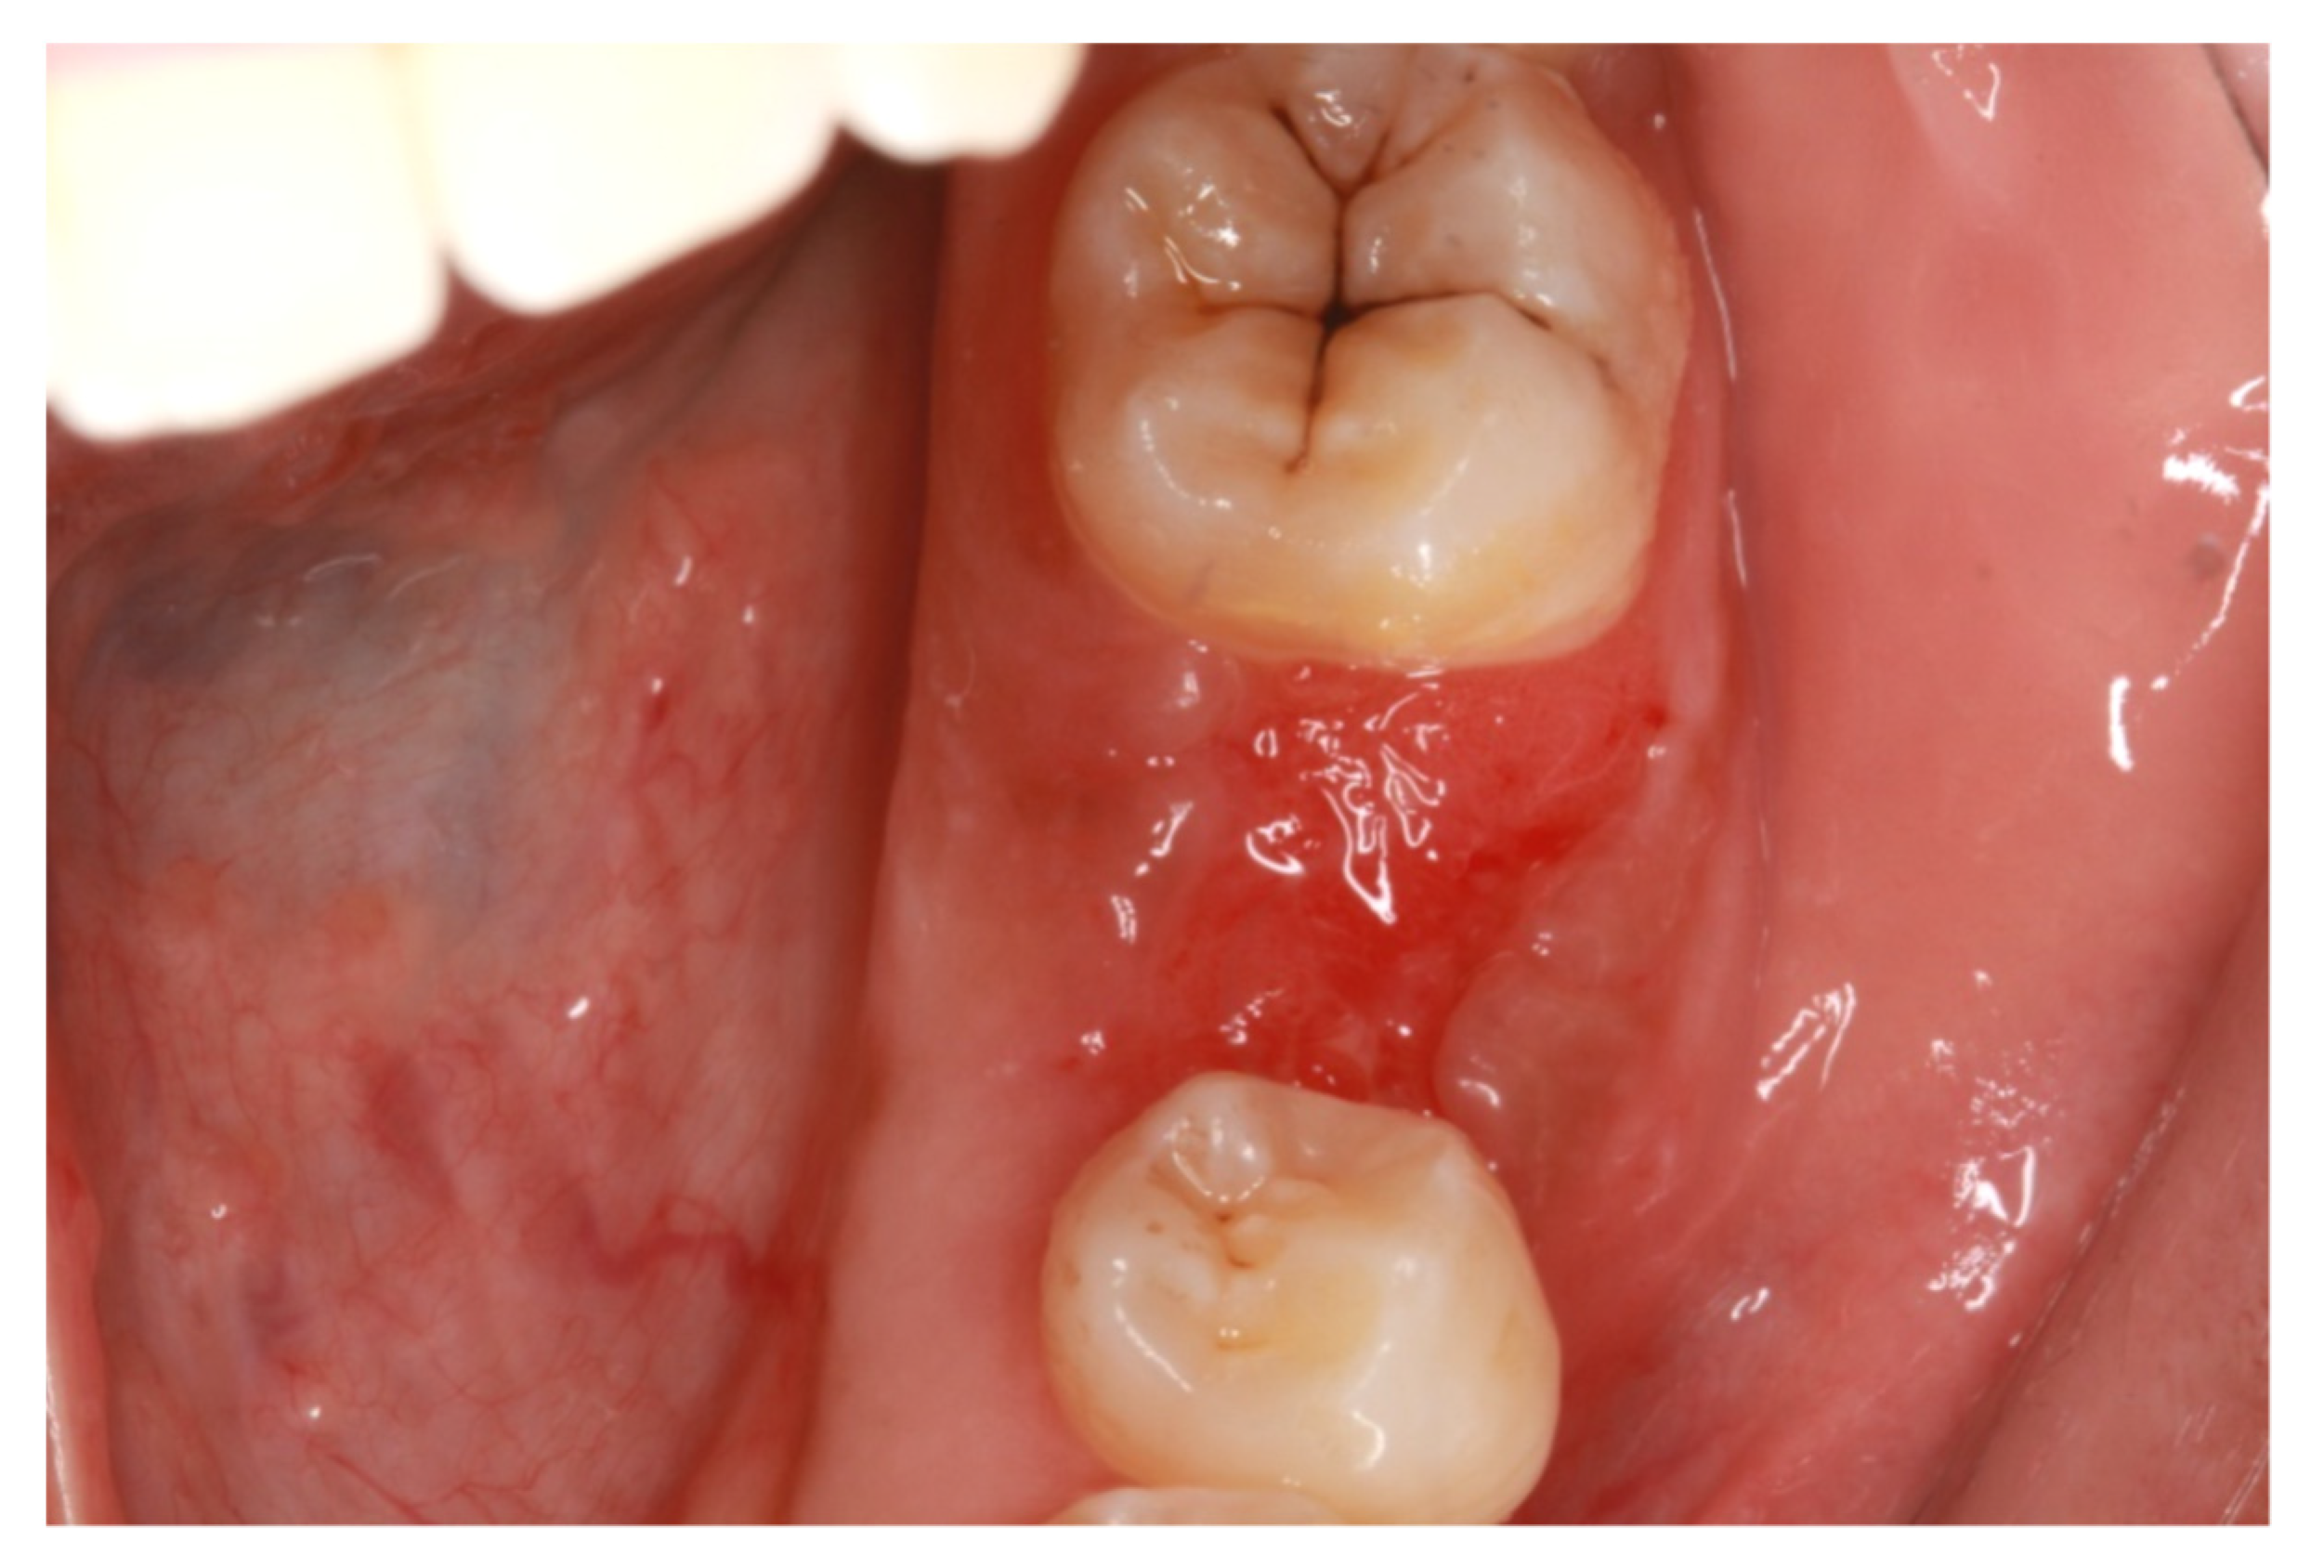

- Alauddin, M.S.; Ramli, H. Management of Membrane Exposure Utilizing Concentrated Growth Factor (CFG) in Guided Bone Regeneration: A Clinical Report. Open Dent. J. 2020, 14, 763–768. [Google Scholar] [CrossRef]